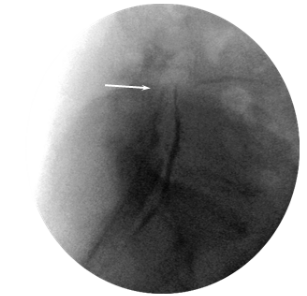

On the assumption of localization of the affected roots, we used classic caudal access to locate the introducer. From paramedian access, a puncture was performed in the hiatus sacralis; the Tuohy 16G introducer was placed at a level not higher than S3. The RCE electrode was moved through the introducer in the direction of the lumbar roots through the dorsal epidural space (Figure 1). There was no special protocol of fluid administration for hydrodissection or facilitating electrode conduction. The working tip of the electrode (15 mm) was located in the projection of the lateral canal opposite the exit zone and just dorsal to the affected nerve root, at the exact location of the determined nerve impairment or slightly proximal (Figure 2). After placement of the electrode, sensory stimulation was performed at 50 Hz, in the range of 0.3-0.5 V, and a typical sensation response was obtained that accurately overlapped the painful area of the patient. Because theventral and dorsal branches are very close in the impact zone, motor stimulation with 2 Hz was often also effective, but with a slightly higher voltage, most often within 1 V. Provided that the impedance in the impact zone corresponded to a normal value (200–400 Ohm), the PRF was started in monopolar mode with the following characteristics: frequency 2 Hz (20 ms pulse, 480 ms pause), amplitude 65V, exposure time 360 ​​sec, temperature in the action zone not exceeded 42 degrees Celsius. After the procedure, a water-soluble steroid was administered (dexamethasone, 8 mg) through the catheter (Figure 3). Patients remained in the hospital for at least 2 hours, upon expiration of the control period, and in the absence of warning signs, they were discharged home.

Figure 1 Lateral view. Introducer and RCE electrode in the sacral canal. Arrow – tip of the electrode.